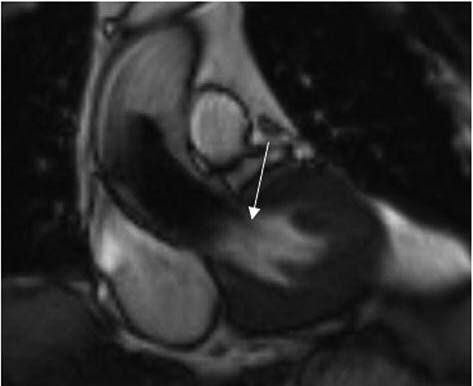

Процедура TAVI включает в себя баллонную предилатацию нативного аортального клапана и установку биопротеза внутри естественного каркаса, образованного кальцинированными створками и фиброзным кольцом. Массивный асимметричный кальциноз створок, неадекватный выбор типа и размера транскатетерного протеза и ошибки в его позиционировании могут привести к возникновению ПАР. Наряду с развитием нарушений ритма и проводимости, ПАР является наиболее значимым осложнением операций TAVI (рис. 3). Потенциально связано с ПАР и нарушение систолической функции правого желудочка на ранней стадии после TAVI [26]. По мнению большинства исследователей, пациенты с ПАР имеют худший отдаленный прогноз. Умеренная или тяжелая аортальная регургитация после TAVI является независимым предиктором смертности в послеоперационном периоде от 30 дней до 1–2 лет. Связь ПАР с повышенной смертностью отмечена в исследовании PARTNER. В исследовании W. Kodali 2015 г. показано, что в течение года после проведения замены аортального клапана повышение смертности от сердечно-сосудистых заболеваний и повторная госпитализация коррелировали с прогрессированием ПАР [27].

Рис. 3. МР-изображение после транскатетерной трансфеморальной малоинвазивной имплантации аортального клапана (собственное наблюдение). Стрелкой указан низкоинтенсивный поток ПАР.

Высказывается мнение, что трансторакальная ЭхоКГ недооценивает ПАР и уступает в этом МРТ, которая не подвержена влиянию артефактов от протеза, позволяет проводить полное количественное определение объема регургитации независимо от типа клапана и количества струй. Кроме того, с помощью МРТ выполняется комплексная оценка последствий ПАР, влияющих на объем и функцию ЛЖ [28, 29].